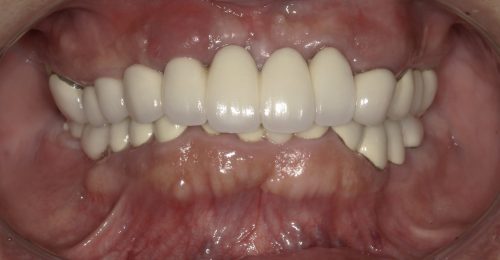

• オールオン4(上顎5本下顎4本)

術前

術後

年齢・性別 63歳・男性

治療期間 5ヶ月、通院回数18回

治療費用 5,720,880円(税込)

治療内容 歯周病により歯が動揺し噛めない状態。仕事に差し支えないように話しやすく、口元も綺麗にしたい。しっかり噛めるようにしたい。